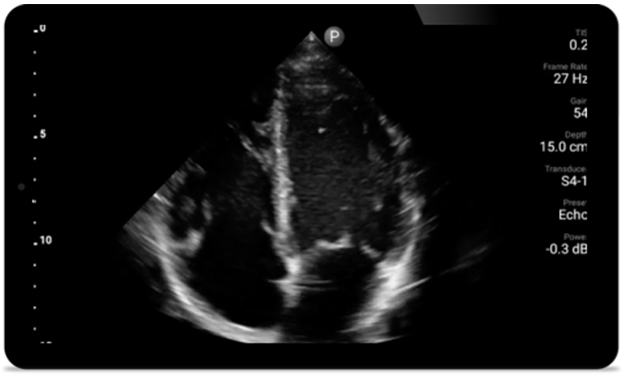

Every second counts in cardiac care

Heart attack patients need immediate care. Lumify's cardiac presets can help patients get diagnosed faster to improve their outcomes.

• 4 to 1 MHz extended operating frequency range • 2D, color Doppler, M-mode, advanced XRES and multivariate harmonic imaging • High-resolution imaging for abdominal and cardiac applications: Cardiac, OB/GYN, Lung, Abdomen and FAST imaging preset optimizations Lumify aids life-saving technology in prehospital setting